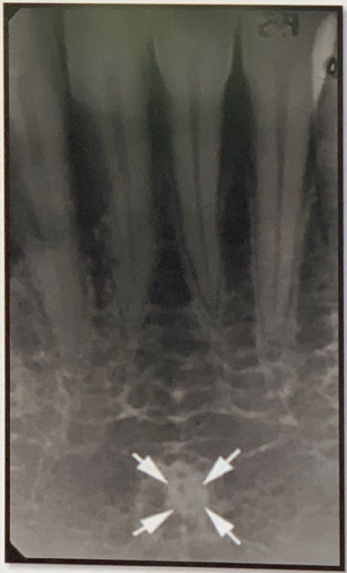

85. What is showing by arrow?

Genial Tubercles (Mental Spine) bony protuberances located on the lingual surface of the mandible slightly above the inferior border and in the midline. serve to attach the genioglossus muscles (at the superior tubercles) and the geniohyoid muscles (at the inferior tubercles) to the mandible. Usually well visualized on mandibular occlusal radiographs as one or more small projections.